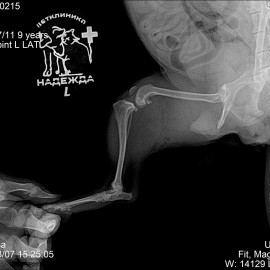

Наш пациент собака породы йоркширский терьер возрастом 9 лет по кличке Клара.

Обратились в клинику с жалобами на хромоту на левую тазовую конечность в течение нескольких дней. Хромота развилась остро.

После проведенных исследований был поставлен диагноз: разрыв передней крестообразной связки левого коленного сустава, медиальный пателлярный вывих левого коленного сустава. Были проведены операции: артротомия левого коленного сустава, трохлеопластика блока левого бедра, дупкликатура капсулы коленного сустава, латеральная транспозиция шероховатости левой большеберцовой кости, латеральная траспозиция шероховатости большеберцовой кости, TPLO.

Снимок 1 до операции.